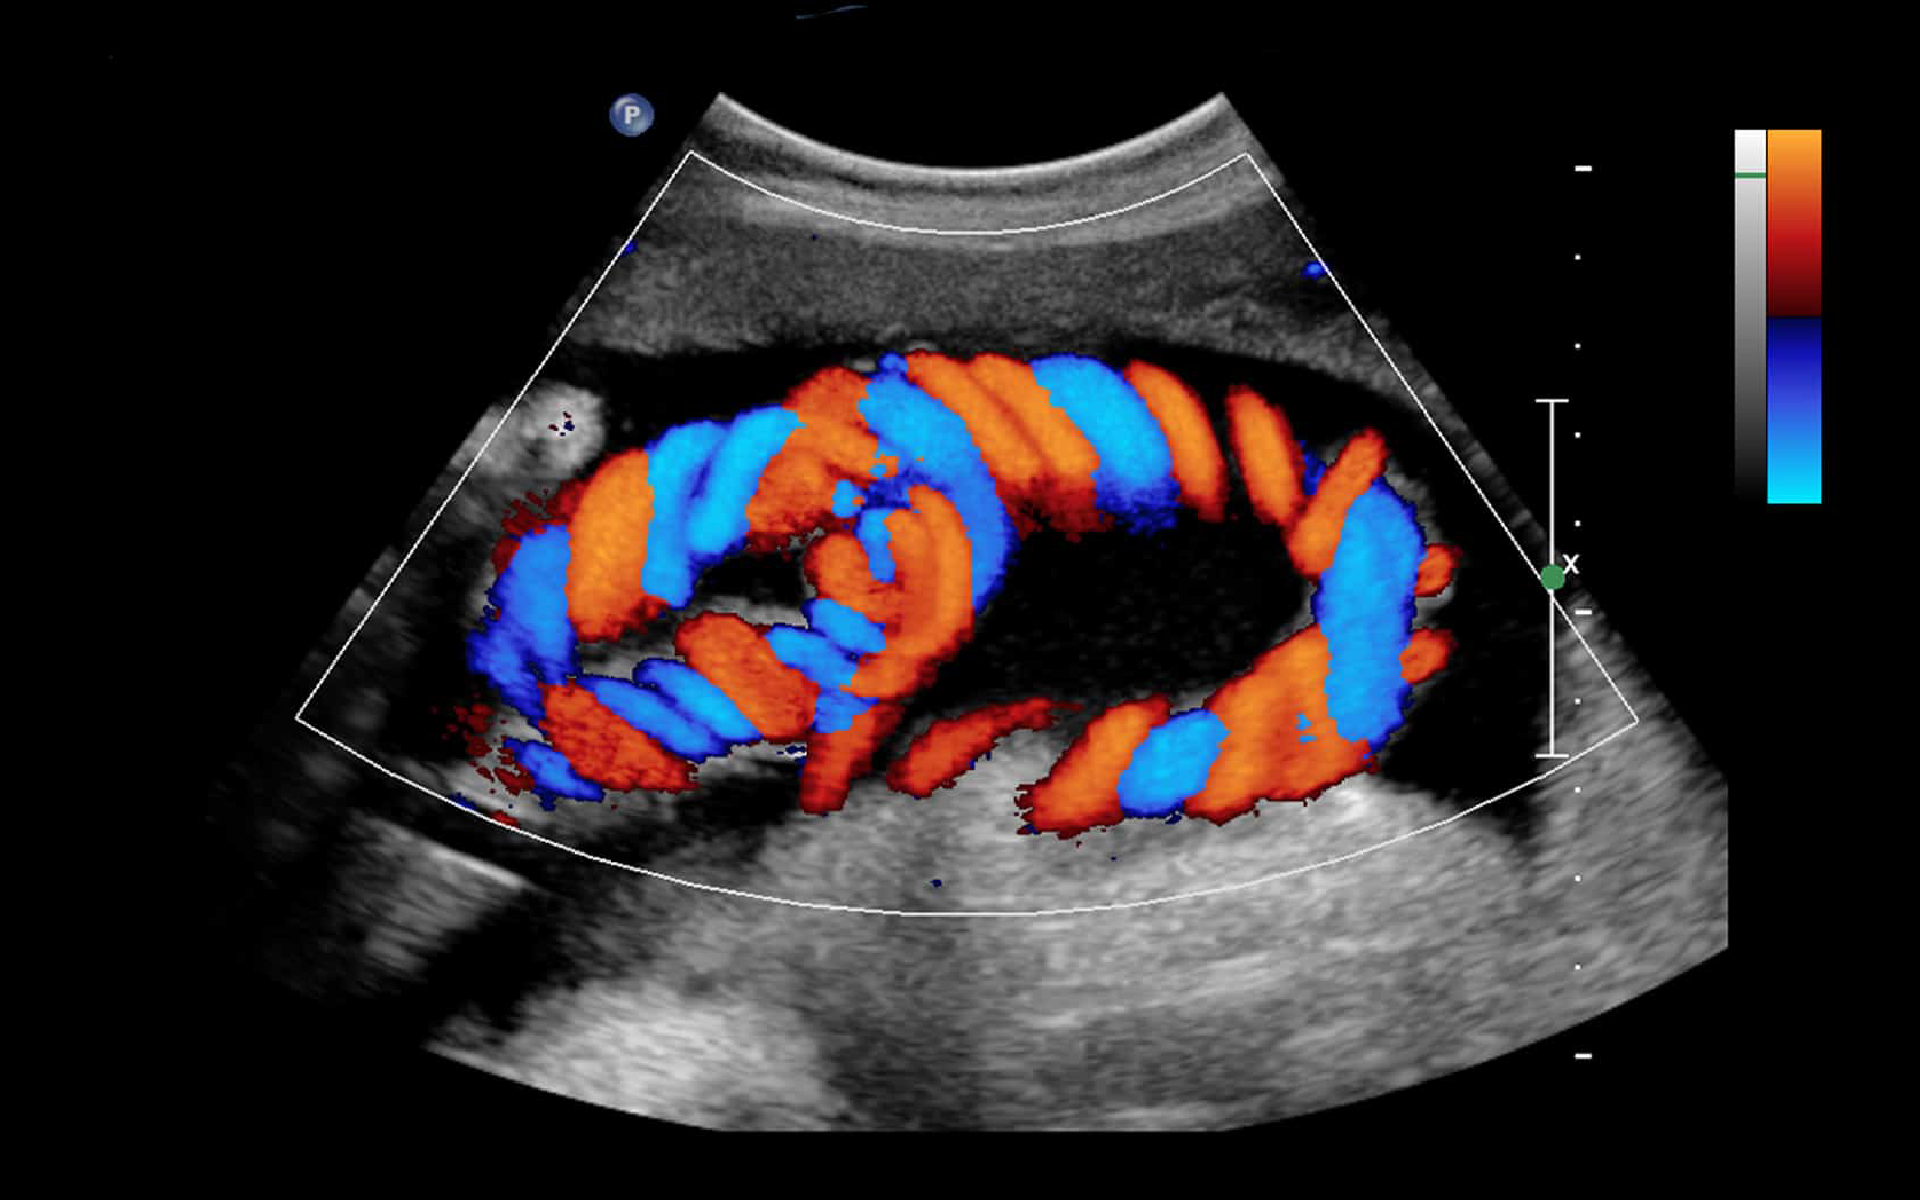

A Colour Doppler Scan is a critical diagnostic tool used to visualize and measure blood flow through your blood vessels. At Liberty Healthcare, we provide the most reliable Colour Doppler scan in Malad and Goregaon, utilizing high-frequency sound waves to provide real-time color-coded images of circulation.

Our facility, located near Liberty Garden, Malad West, is equipped with state-of-the-art ultrasound machines. We specialize in obstetric dopplers, ensuring that expectant mothers in Goregaon and Kandivali receive the highest level of fetal monitoring and placental health assessment.